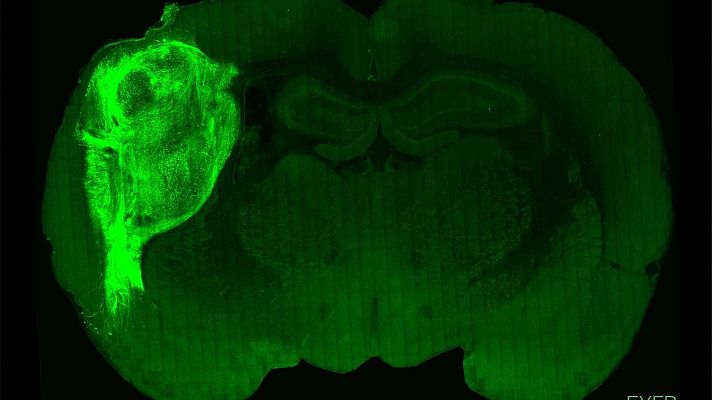

Implantan 'minicerebros' humanos en ratas recién nacidas y logran influir en su comportamiento

Un equipo de científicos de la Universidad de Stanford en EEUU ha conseguido trasplantar neuronas humanas al cerebro de ratas recién nacidas y...